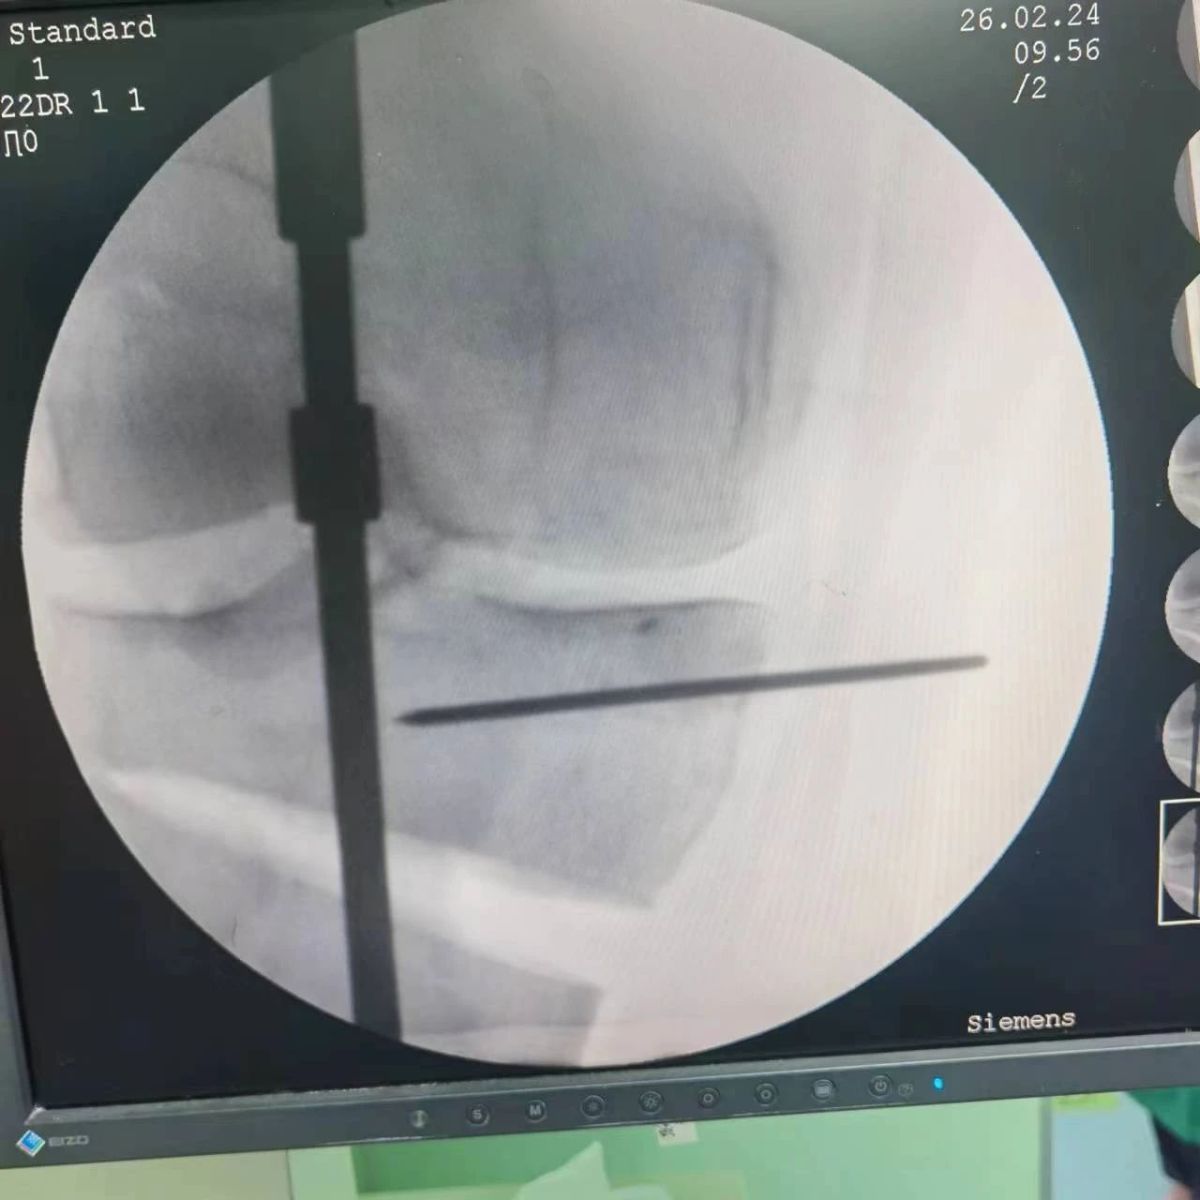

李付彬主任團(tuán)隊(duì)通過(guò)精準(zhǔn)術(shù)前規(guī)劃,設(shè)計(jì)目標(biāo)力線及調(diào)整撐開(kāi)角度,轉(zhuǎn)化成需要撐開(kāi)的高度,最終設(shè)計(jì)出同等高度的填充塊,術(shù)中驗(yàn)證力線調(diào)整與術(shù)前規(guī)劃完全一致!

鋼板位置、螺釘位置及長(zhǎng)度均可通過(guò)術(shù)前規(guī)劃計(jì)算,術(shù)中通過(guò)定位操作,基本與術(shù)前規(guī)劃一致,手術(shù)快速高效完成,外側(cè)合頁(yè)保留完整。無(wú)任何并發(fā)癥出現(xiàn)。術(shù)后見(jiàn)鋼板位置及力線糾正近乎完美!